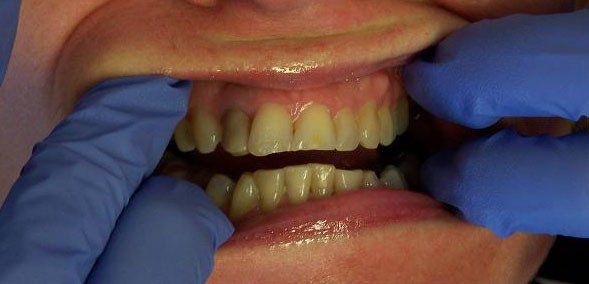

Ally Before

Holly Before

Johnson Before

Karen Before

Nancy Before

Ralph Before

Steve Before